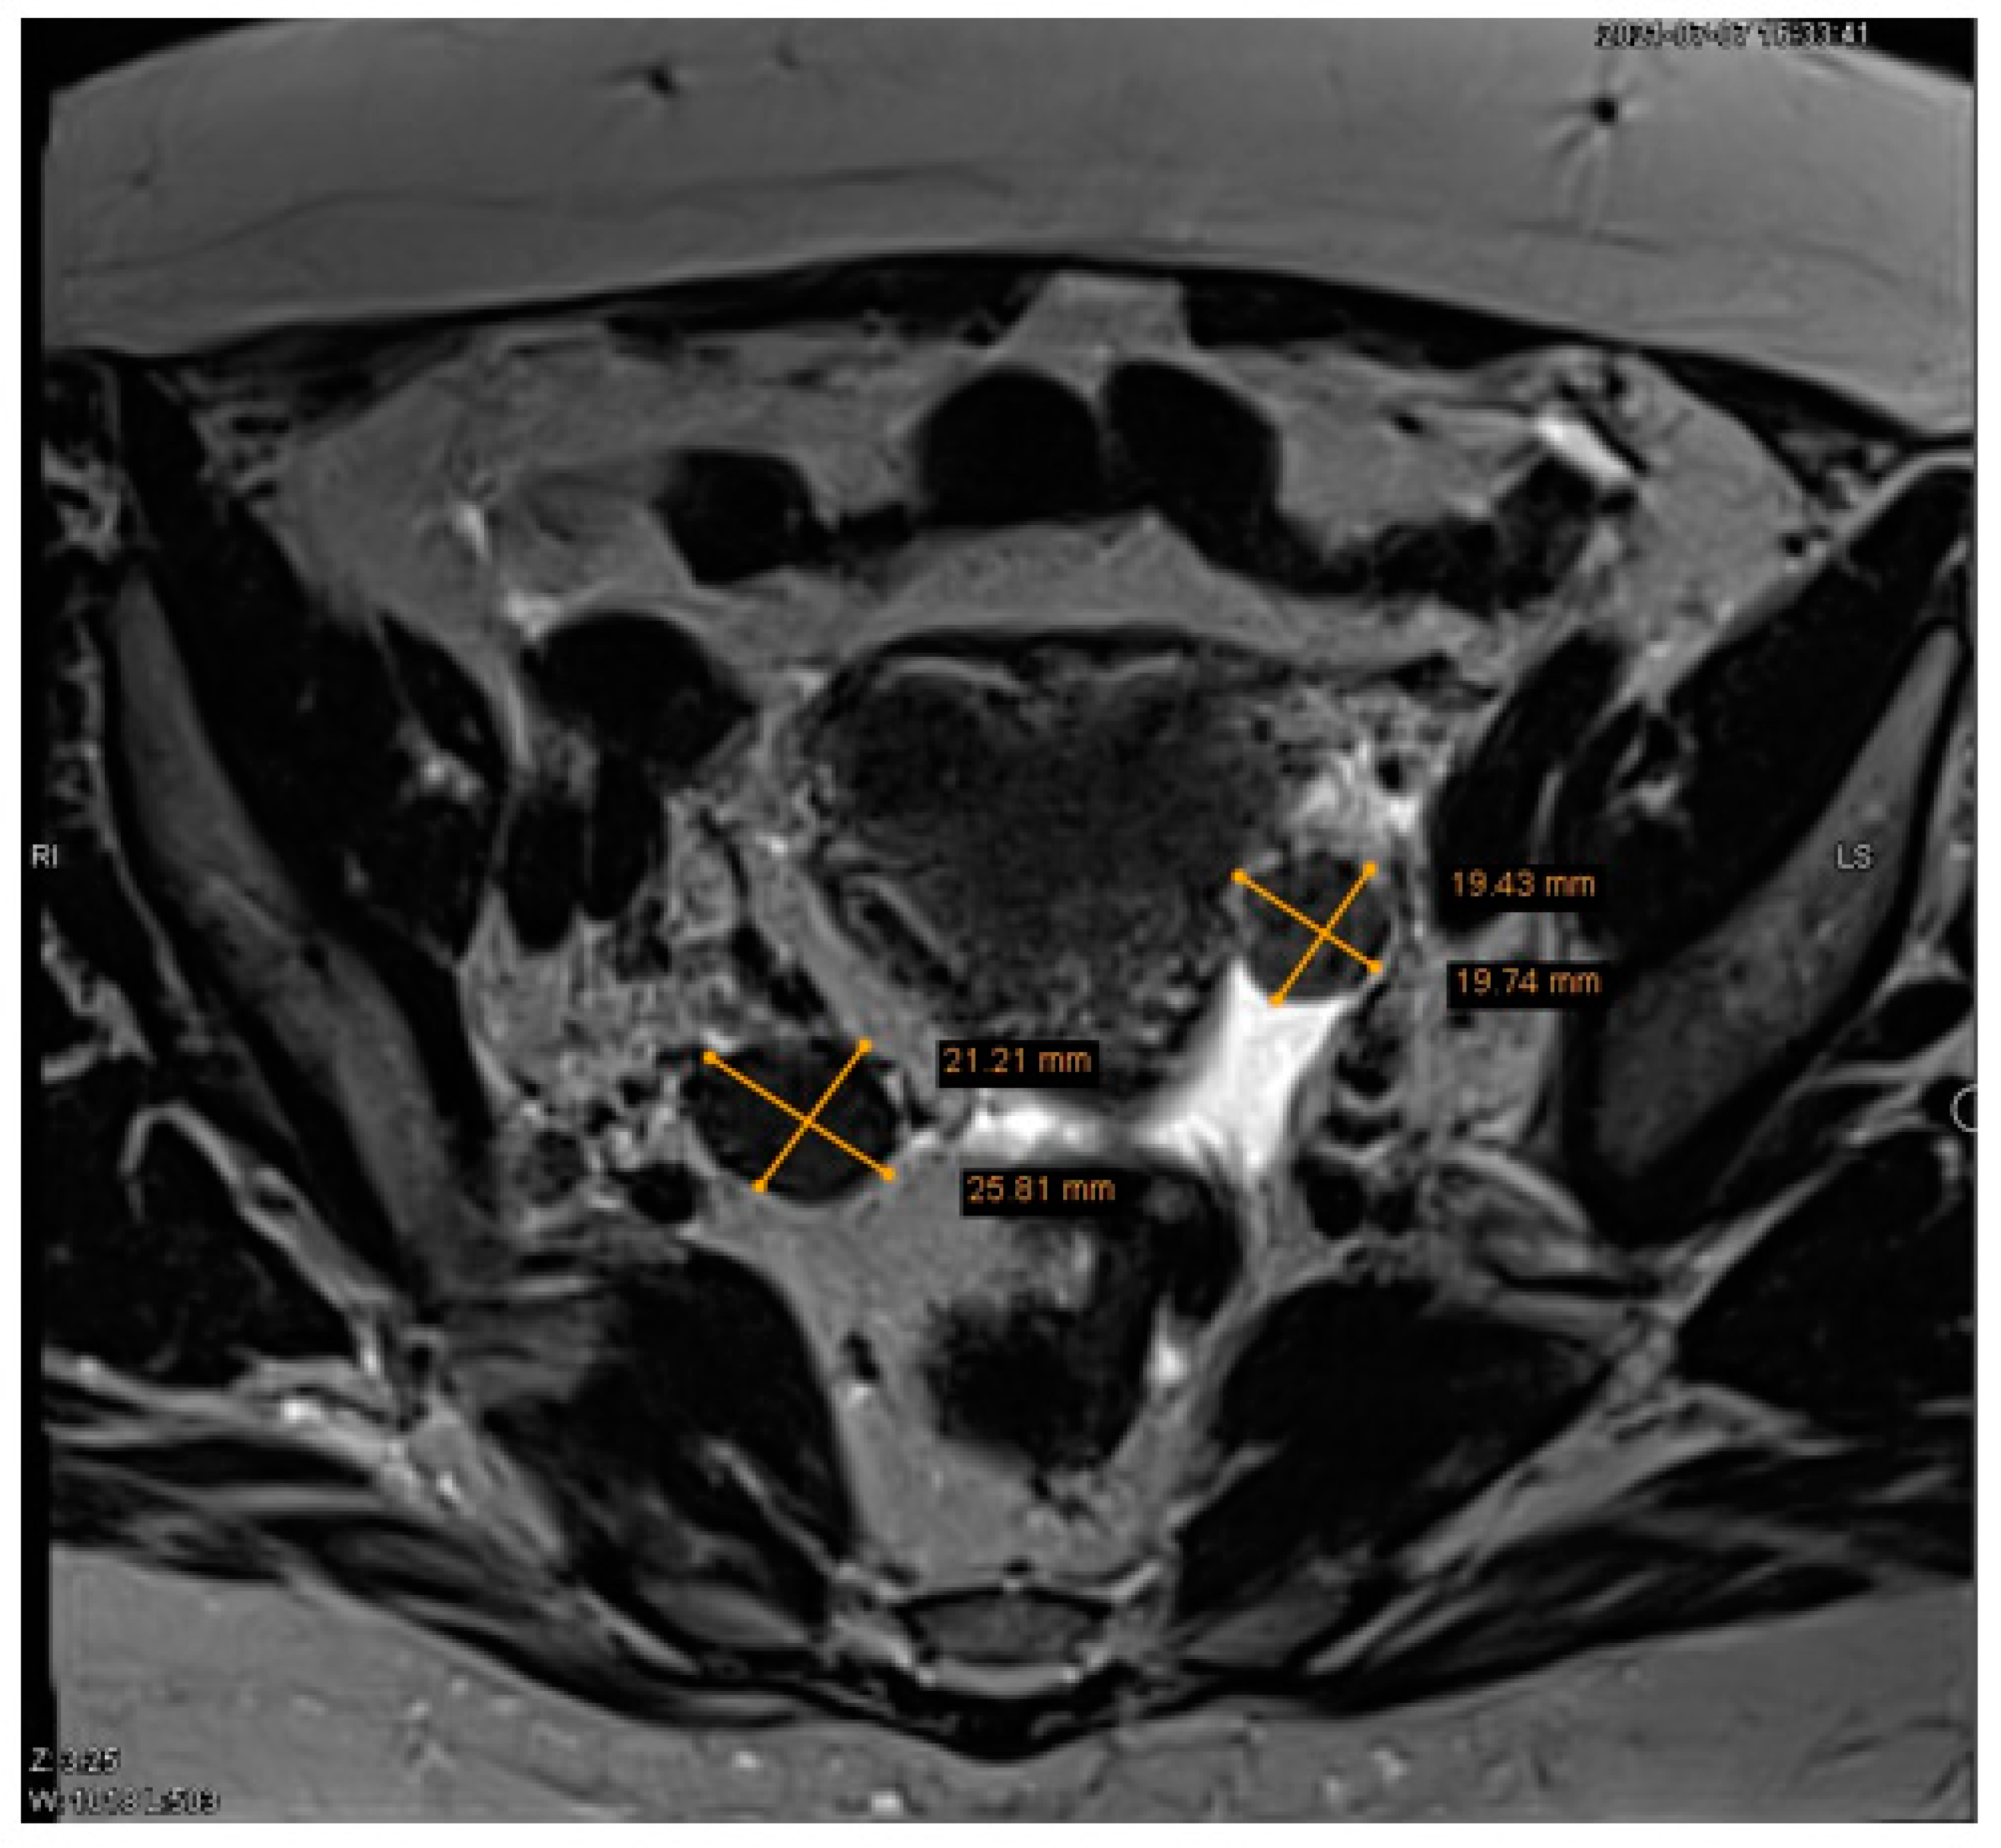

Subsequently, the patient was referred to the gynaecology department due to suspected ovarian tumors of unknown aetiology. Ovarian tumor markers were conducted for the patient and they were within normal ranges (cancer antigen 125 (CA-125) 25.5 kU/L (normal range, <35) and human epididymis 4 (HE4) 31.6 pmol/L (normal range, <140)). A pelvic MRI confirmed the presence of two low-intensity masses in ovaries bilateral, with the left mass measuring 1.9 × 1.9 cm and the right mass measuring 2.1 × 2.6 cm (Figure 2). Additionally, a small amount of free fluid in the pelvis was observed.

Figure 2. Pelvic magnetic resonance imaging (MRI) of two ovarian lesions. The pelvic MRI revealed a circumscribed left ovarian structure measuring 1.9 × 1.9 cm and a circumscribed right ovarian structure measuring 2.1 × 2.6 cm.